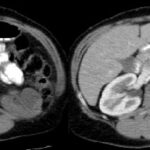

Fase excretora o arterial tardía

Comienza aproximadamente a los 3 minutos posteriores a la inyección del medio de contraste y permite evaluar su excreción por el sistema colector; por lo tanto, es útil para evaluar la relación de la masa con los cálices y la pelvis renal y llegar a una mejor planificación quirúrgica conservadora en un caso dado 3-4 (Fig. 4).